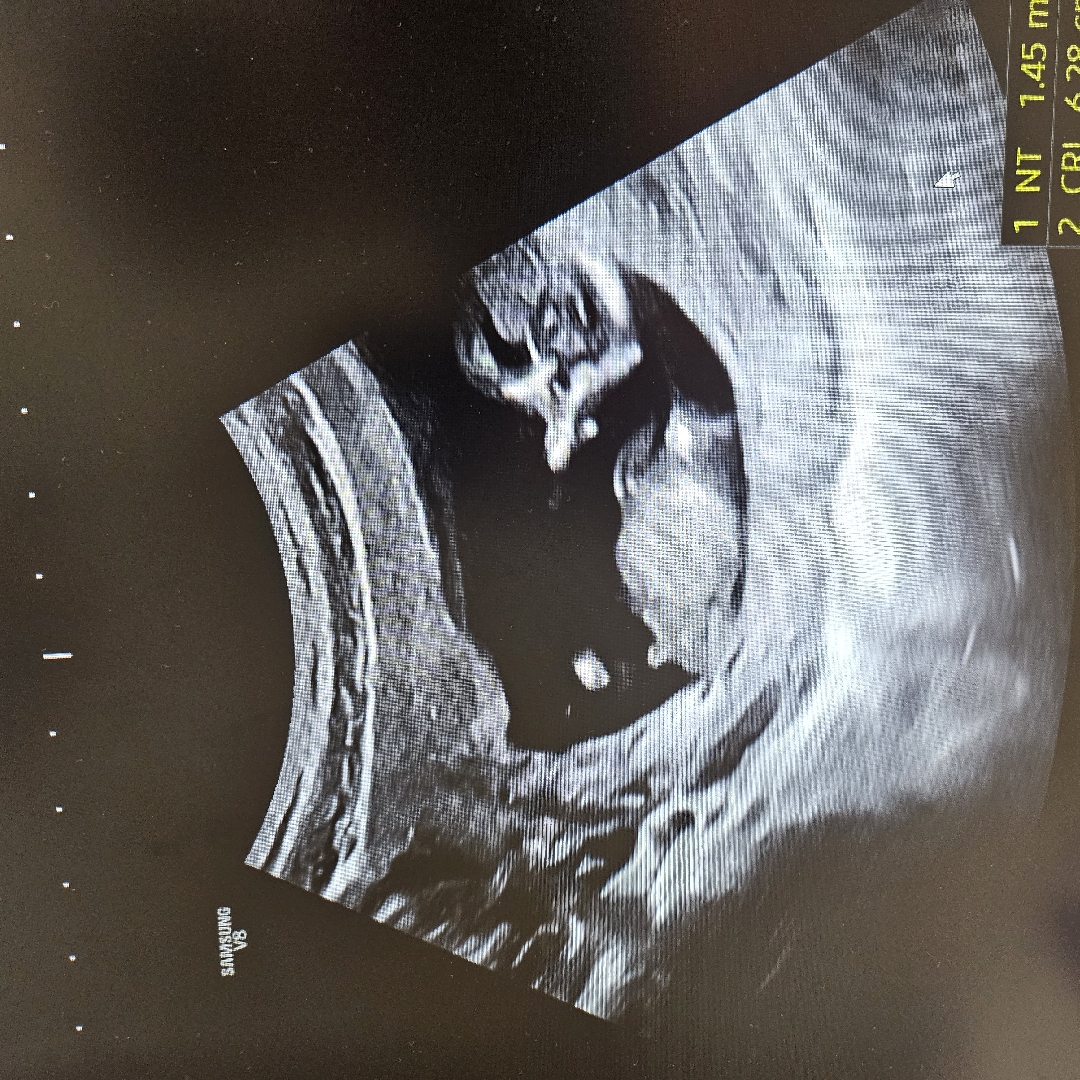

혹시 아들일까요?!

안녕하세요 혹시 아들일까요?! 각도법의 천재님들 알려주세요

와 이건 아들맞네요

아들이에요 첫째 아들이랑 각도가 똑같아용 ㅎㅎ

아들이네요 저희도 저래서 아들로